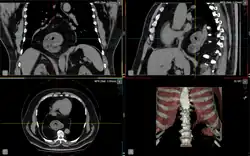

Die paraösophageale Hiatushernie (siehe Abbildung, Buchstabe D) zeichnet sich aus durch die anatomisch korrekte Lage des unteren Ösophagussphinkters (Schließmuskel der Speiseröhre) und dessen uneingeschränkte Funktion. Ein Teil des Magens schiebt sich jedoch von unten in den Brustraum. In der äußersten Form dieser Hiatushernie kann auch der ganze Magen oberhalb des Zwerchfells liegen (Upside-Down-Stomach oder Thoraxmagen). Im klinischen Verlauf beginnt die paraösophageale Hiatushernie mit einem asymptomatischen Stadium. Es folgt das unkomplizierte Stadium, mit Aufstoßen und Druckgefühl in der Herzgegend. Diese Symptome treten vor allem nach der Nahrungsaufnahme auf. Danach kommt es zum Komplikationsstadium mit Passagestörungen, Inkarzerationen, Geschwüren und Blutarmut infolge chronischer Blutungen.